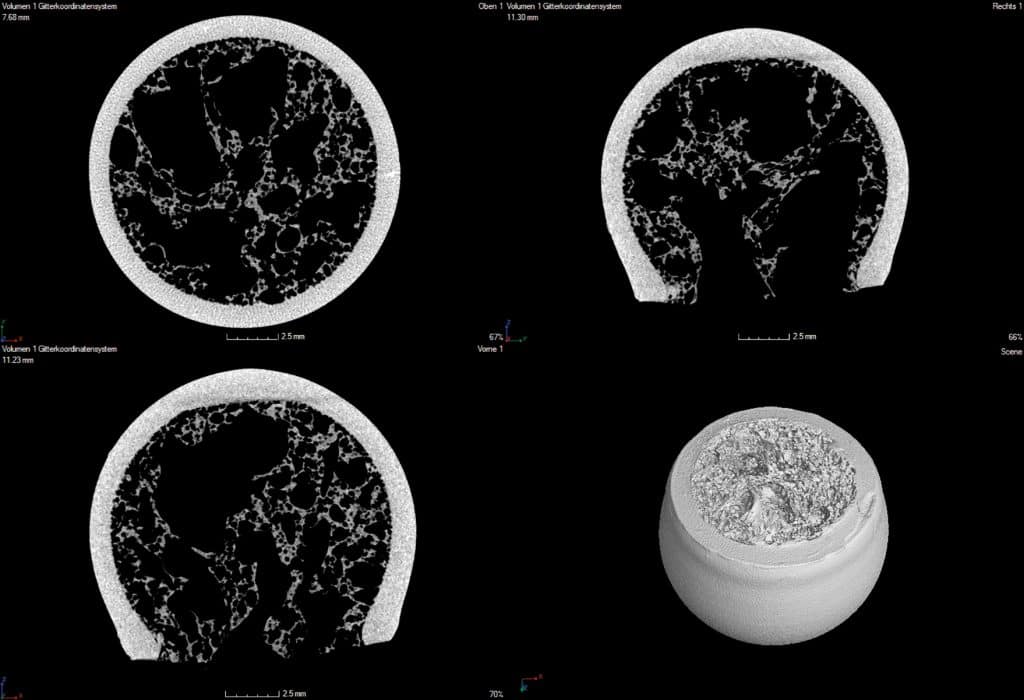

Figure 1. : Bone replacement testing parts after sintering - the “cortical” component was made by LCM, the “trabecular” structure by freeze foaming.

After removal of the frozen suspension media by a subsequent sublimation process, the ceramic green foam is sintered. As a result, ceramic foam has been generated showing a bimodal pore size distribution – large pores of 400–800µm in the foam cells and 40-60nm in the ligaments of the foam. Such freeze foam made of hydroxyapatite has been proven to show advantageous ingrowth conditions for mesenchymal human stem cells_7. After sublimation drying, the parts had been debindered and co-sintered (at 1350°C) to one bio composite as can be seen in Figure 1. From the computed tomography images (Figure 2) it becomes visible that the “trabecular” foam structure and the “cortical” LCM structure form a uniform component with a firm material fit devoid of cracks in the interface region.

Figure 2. Computed tomography images of bone replacement testing parts showing defect-free interfaces between “trabecular and cortical” structure.